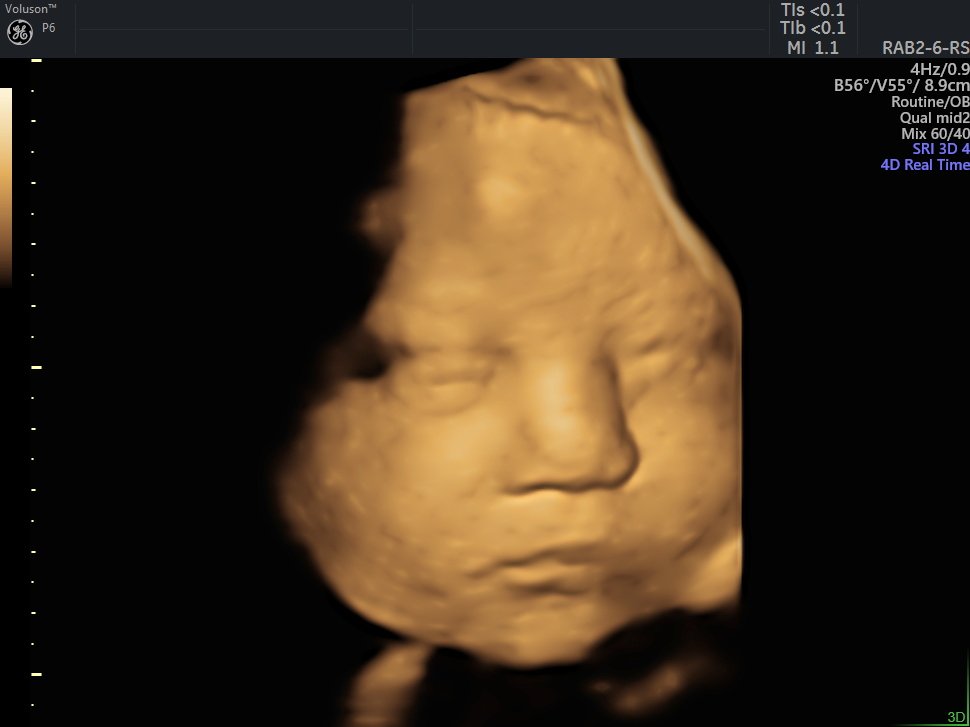

4 Boyutlu (Renkli) Ultrason ve Doppler Ultrasonografi

4 D Ultrasonografi